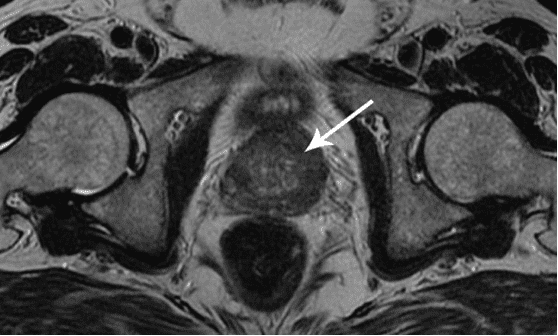

Želim da vam pokažem neke fotografije tako da sami možete da vidite šta se dešava urogenitalnom sistemu i drugim organima muškarca koji nema seksualne odnose.

Evo kako izgleda upala prostate uzrokovana stagnacijom sperme (kada se testisi ne prazne). Trajna upala dovodi do adenoma prostate, a kasnije do raka prostate (prema statistikama, 38% muškaraca umire zbog ovoga). Zbog odsustva seksa, ovo se dešava uvek i to je razlog zašto se adenom prostate naziva "bolešću starih".

Zbog stagnacije dolazi do nakupljanja holesterola na zidovima krvnih sudova, a može doći do nastanka trombova. Trombovi povećavaju rizik od nastanka moždanog i srčanog udara. Smrt ovog pacijenta uzrokovao je srčani udar, a njegovo srce je prikazano na ovim fotografijama.